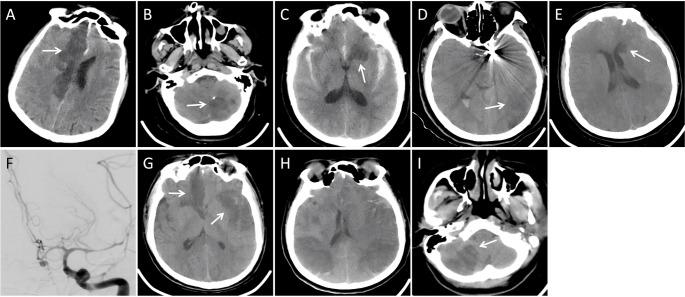

动脉瘤性蛛网膜下腔出血后手术相关脑梗死的危险因素。

Risk factors for surgery-related cerebral infarction after aneurysmal subarachnoid hemorrhage.

Surgery-related cerebral infarction (SRCI) is an important complication after aneurysmal subarachnoid hemorrhage (aSAH), and detailed assessment of the characteristics and risk of SRCI is insufficient. We aimed to analyze the risk factors for SRCI in different treatment modalities after aSAH. A total of 472 patients were included in this retrospective study, including 169 in clip and 303 in endovascular. Regarding radiologically observable SRCI as the outcome, we used univariate and multivariate statistical analyses of risk factors and summarized the characteristics of SRCI. The incidence of SRCI was significantly higher in the clipping group compared to the endovascular group (47% vs. 21%, p < 0.001). Patients with SRCI in clip group had higher HH (p = 0.007) and mFisher (p = 0.007) and more diabetics (p = 0.018). They were more likely to receive primary EVD (p < 0.001), decompressive craniectomy (p = 0.022), multiple aneurysms repair (p = 0.008), and had longer procedure time (p = 0.006). Patients with SRCI in endovascular group were older (p = 0.001), more hypertensive (p = 0.001), with higher HH (p = 0.034) and longer procedure time (p = 0.005). They were more likely to presented with acute hydrocephalus (p = 0.030), type-3 aortic arch in pathway (p = 0.009) and proximal stenosis of the parent artery (p = 0.045). Multivariate regression analysis identified diabetes (OR = 7.050, 95%CI: 1.303-38.158), primary EVD (OR = 4.066, 95%CI: 1.567-10.550), longer procedure time (OR = 1.007, 95%CI: 1.001-1.013), and repair multiple aneurysms (OR = 3.916, 95%CI: 1.142-13.432) independently predicted SRCI in clip group. Age (OR = 1.033, 95%CI: 1.001-1.066), hypertension (OR = 2.337, 95%CI: 1.220-4.478), type-3 aortic arch in pathway (OR = 4.010, 95%CI: 1.177-13.666), and proximal stenosis of parent artery (OR = 2.442, 95%CI: 1.015-5.875) independently predicted SRCI in endovascular group. Diabetes, primary EVD, longer procedure time, and repair multiple aneurysms were independent risk factors for SRCI in clip group. In contrast, age, hypertension, type-3 aortic arch in pathway, and proximal stenosis of parent artery were independent risk factors for SRCI in endovascular group.

手术相关性脑梗死(SRCI)是动脉瘤性蛛网膜下腔出血(aSAH)后的一种重要并发症,目前对SRCI的特征和风险的详细评估尚不充分。我们旨在分析aSAH后不同治疗方式下SRCI的危险因素。本回顾性研究共纳入472例患者,其中夹闭术组169例,血管内介入组303例。以影像学可观察到的SRCI作为结局,我们对危险因素进行单因素和多因素统计分析,并总结SRCI的特征。夹闭术组的SRCI发生率显著高于血管内介入组(47%对21%,p<0.001)。夹闭术组发生SRCI的患者有更高的HH评分(p=0.007)和改良Fisher评分(p=0.007),且糖尿病患者更多(p=0.018)。他们更有可能接受一期脑室外引流(EVD)(p<0.001)、去骨瓣减压术(p=0.022)、多个动脉瘤修复(p=0.008),且手术时间更长(p=0.006)。血管内介入组发生SRCI的患者年龄更大(p=0.001)、高血压患者更多(p=0.001),有更高的HH评分(p=0.034)和更长的手术时间(p=0.005)。他们更有可能出现急性脑积水(p=0.030)、路径中有3型主动脉弓(p=0.009)和载瘤动脉近端狭窄(p=0.045)。多因素回归分析确定糖尿病(OR=7.050,95%CI:1.303-38.158)、一期EVD(OR=4.066,95%CI:1.567-10.550)、更长的手术时间(OR=1.007,95%CI:1.001-1.013)和修复多个动脉瘤(OR=3.916,95%CI:1.142-13.432)独立预测夹闭术组的SRCI。年龄(OR=1.033,95%CI:1.001-1.066)、高血压(OR=2.337,95%CI:1.220-4.478)、路径中有3型主动脉弓(OR=4.010,95%CI:1.177-13.666)和载瘤动脉近端狭窄(OR=2.442,95%CI:1.015-5.875)独立预测血管内介入组的SRCI。糖尿病、一期EVD、更长的手术时间和修复多个动脉瘤是夹闭术组SRCI的独立危险因素。相比之下,年龄、高血压、路径中有3型主动脉弓和载瘤动脉近端狭窄是血管内介入组SRCI的独立危险因素。